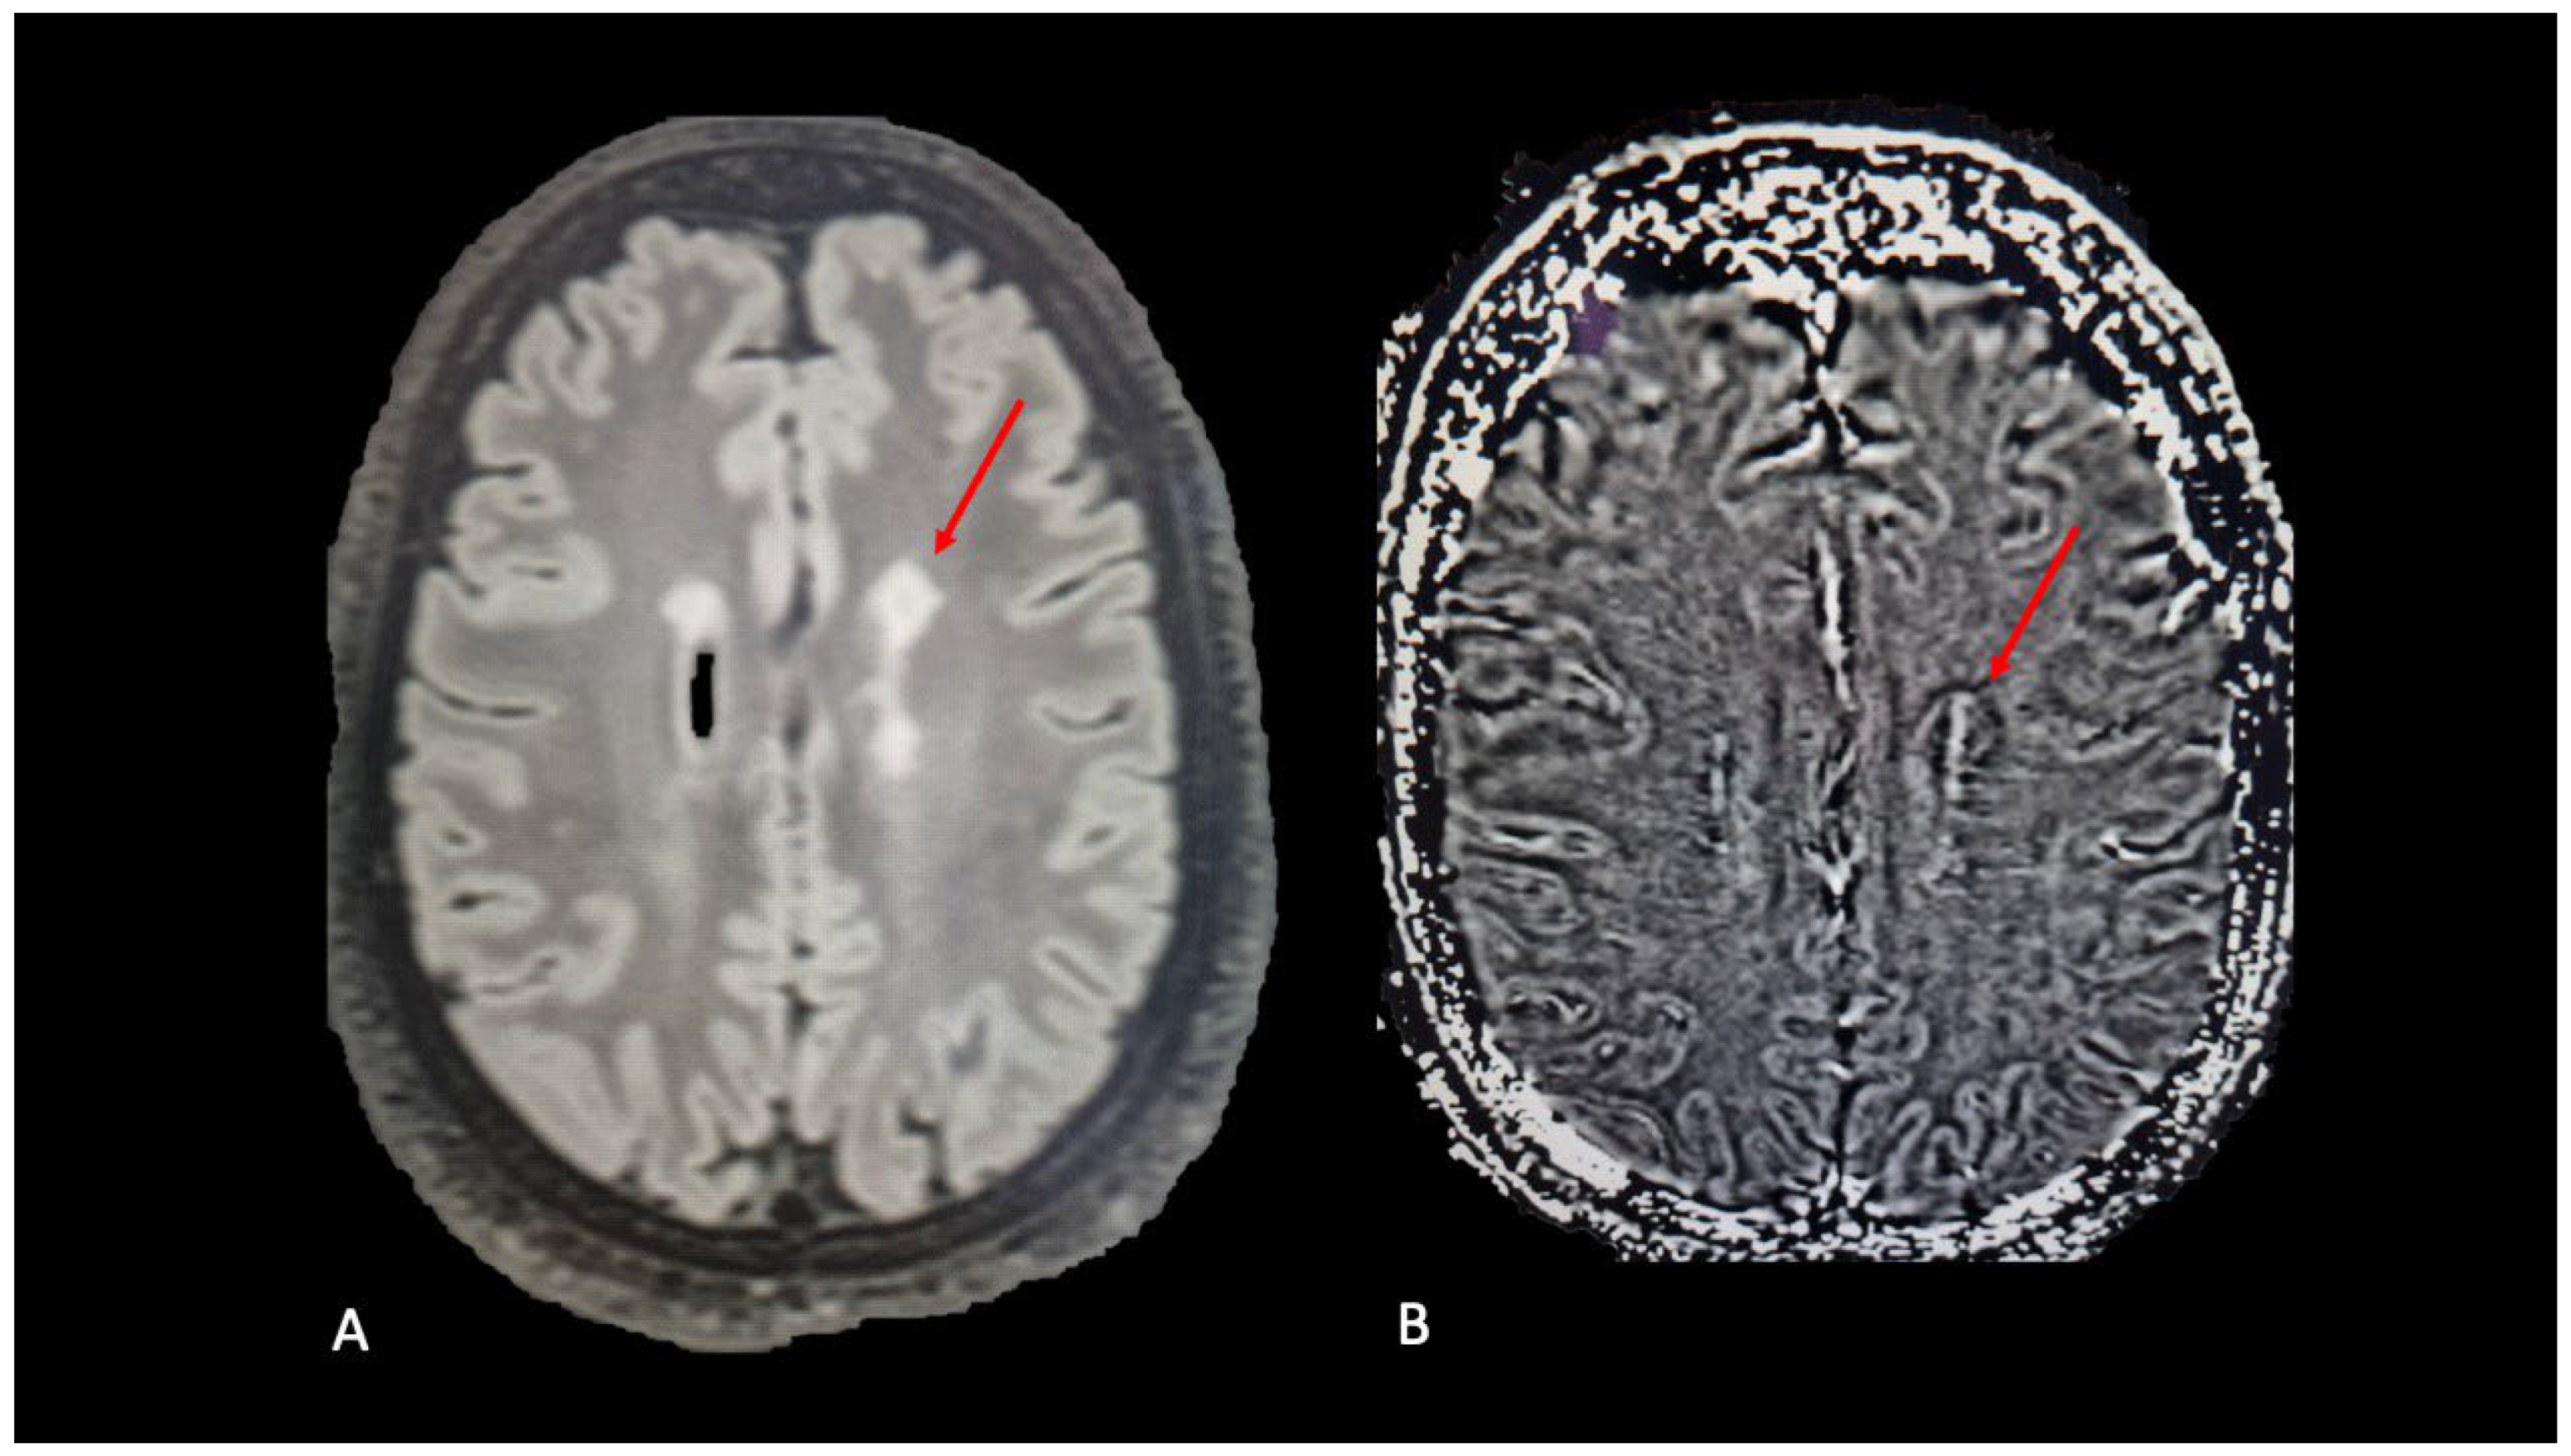

4. Slowly Expanding Lesions

- Elliott, C.; Wolinsky, J.S.; Hauser, S.L.; Kappos, L.; Barkhof, F.; Bernasconi, C.; Wei, W.; Belachew, S.; Arnold, D.L. Slowly expanding/evolving lesions as a magnetic resonance imaging marker of chronic active multiple sclerosis lesions. Mult. Scler. J. 2019, 25, 1915–1925. [Google Scholar] [CrossRef] [PubMed]

- Elliott, C.; Arnold, D.; Chen, H.; Ke, C.; Zhu, L.; Chang, I.; Cahir-McFarland, E.; Fisher, E.; Zhu, B.; Gheuens, S.; et al. Patterning chronic active demyelination in slowly expanding/evolving white matter MS lesions. Am. J. Neuroradiol. 2020, 41, 1584–1591. [Google Scholar] [CrossRef]

- Preziosa, P.; Pagani, E.; Meani, A.; Moiola, L.; Rodegher, M.; Filippi, M.; Rocca, M.A. Slowly Expanding Lesions Predict 9-Year Multiple Sclerosis Disease Progression. Neurol. Neuroimmunol. Neuroinflamm. 2022, 9, e1139. [Google Scholar] [CrossRef] [PubMed]